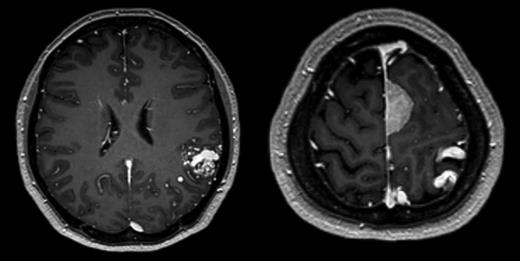

A 56-year-old female presented following a single tonic clonic seizure. Neurological examination was unremarkable. An MRI scan revealed a left posterior frontal parafalcine meningioma with vasogenic oedema in the precentral gyrus with a localized mass effect. In addition, there was a 2.6-cm left parietal AVM located in the left angular/supramarginal gyrus (Fig. 1). There was no evidence of prior haemorrhage. Cerebral angiography confirmed the arterial supply to be predominantly from enlarged parietal and angular branches of the left middle cerebral artery. Venous drainage was superficial into an enlarged vein of Trolard towards the superior sagittal sinus (Fig. 2).

Axial T1-weighted gadolinium-enhanced MRI showing a 2.6-cm left parietal AVM located in the left angular/supramarginal gyrus (left) and an enhancing posterior frontal parafalcine meningioma in close association with the superficial draining veins of the AVM.